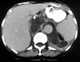

Abdominal abscess